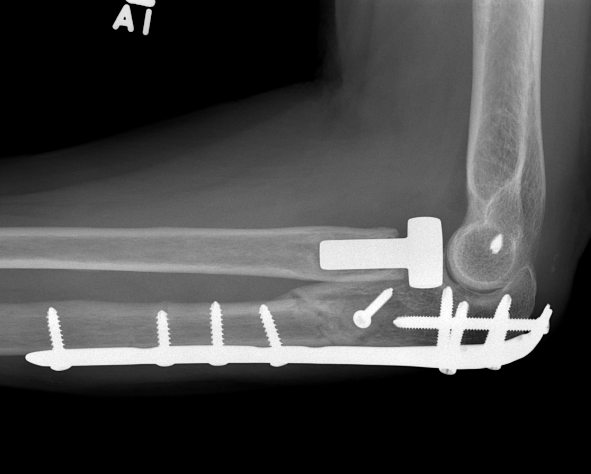

Olecranon plate + ORIF Type II coronoid process + radial head replacement

Olecranon plate with radial head replacement

Olecranon plate with radial head replacement + LCL repair

Olecranon plate + medial coronoid buttress plate + radial head replacement